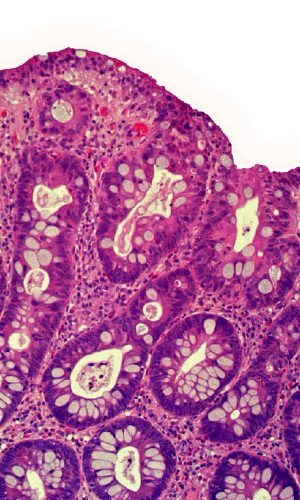

Dr. Shihabi received his anatomic and clinical pathology training at UCSF, completing his surgical pathology fellowship at UCSF with an intense focus on gastrointestinal pathology. Dr. Shihabi is board-certified in Clinical and Anatomic Pathology. At CoCoPath, we offer a breadth of expertise and experience in the diagnosis of various gastrointestinal disorders, including: